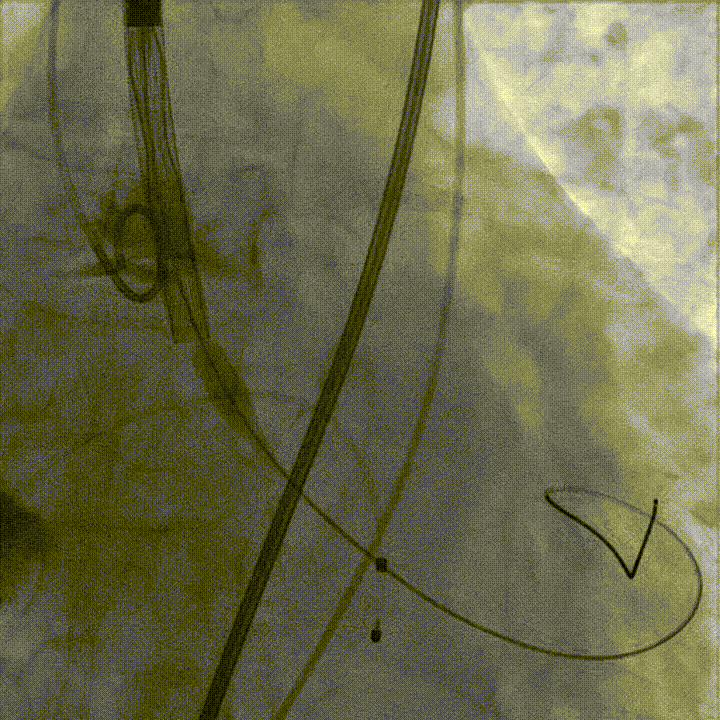

首次释放瓣膜尝试零位释放,当瓣膜释放到一半时行主动脉根部造影,发现瓣膜释放位置偏低,遂回收瓣膜重新定位后再次释放,当瓣膜释放一半时再行主动脉根部造影,发现瓣膜位置良好,遂完全释放瓣膜。